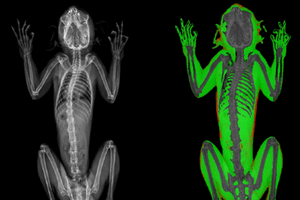

The iNSiGHT technology employs dual energy X-rays to provide highly accurate and repeatable body composition assessments. The system categorizes each pixel into one of three compartments: fat mass, non-bone/lean mass, or bone mineral content, and provides measurements such as bone mineral density, bone mineral content, bone area, tissue area, fat tissue percentage and weight, lean tissue percentage and weight, and total weight in grams.

Comprehensive set of images and parameters

The X-ray attenuated image, bone mineral density map, and color map are produced in a single scan (25 seconds).

X-Ray Attenuation Image - Rat. Image Credit: Scintica Instrumentation Inc

Color Image - Rat. Image Credit: Scintica Instrumentation Inc

Bone Mineral Density Image - Rat. Image Credit: Scintica Instrumentation Inc